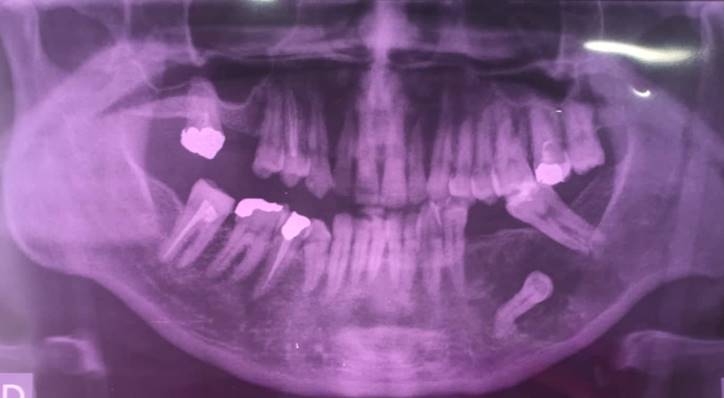

A panoramic radiograph revealed the presence of an unilocular radiolucent lesion extending from the first premolar to the second molar on the left side around the unerupted second premolar tooth (Figure 2). A cone beam computed tomography (CBCT) depicted a well-defined unilocular osteolytic lesion and showed the extent of the bone destruction. (Figure 3)

Figure 2. Initial orthopantomography (OPG) showed a unilocular radiolucent lesion encompassing the impacted second lower premolar.